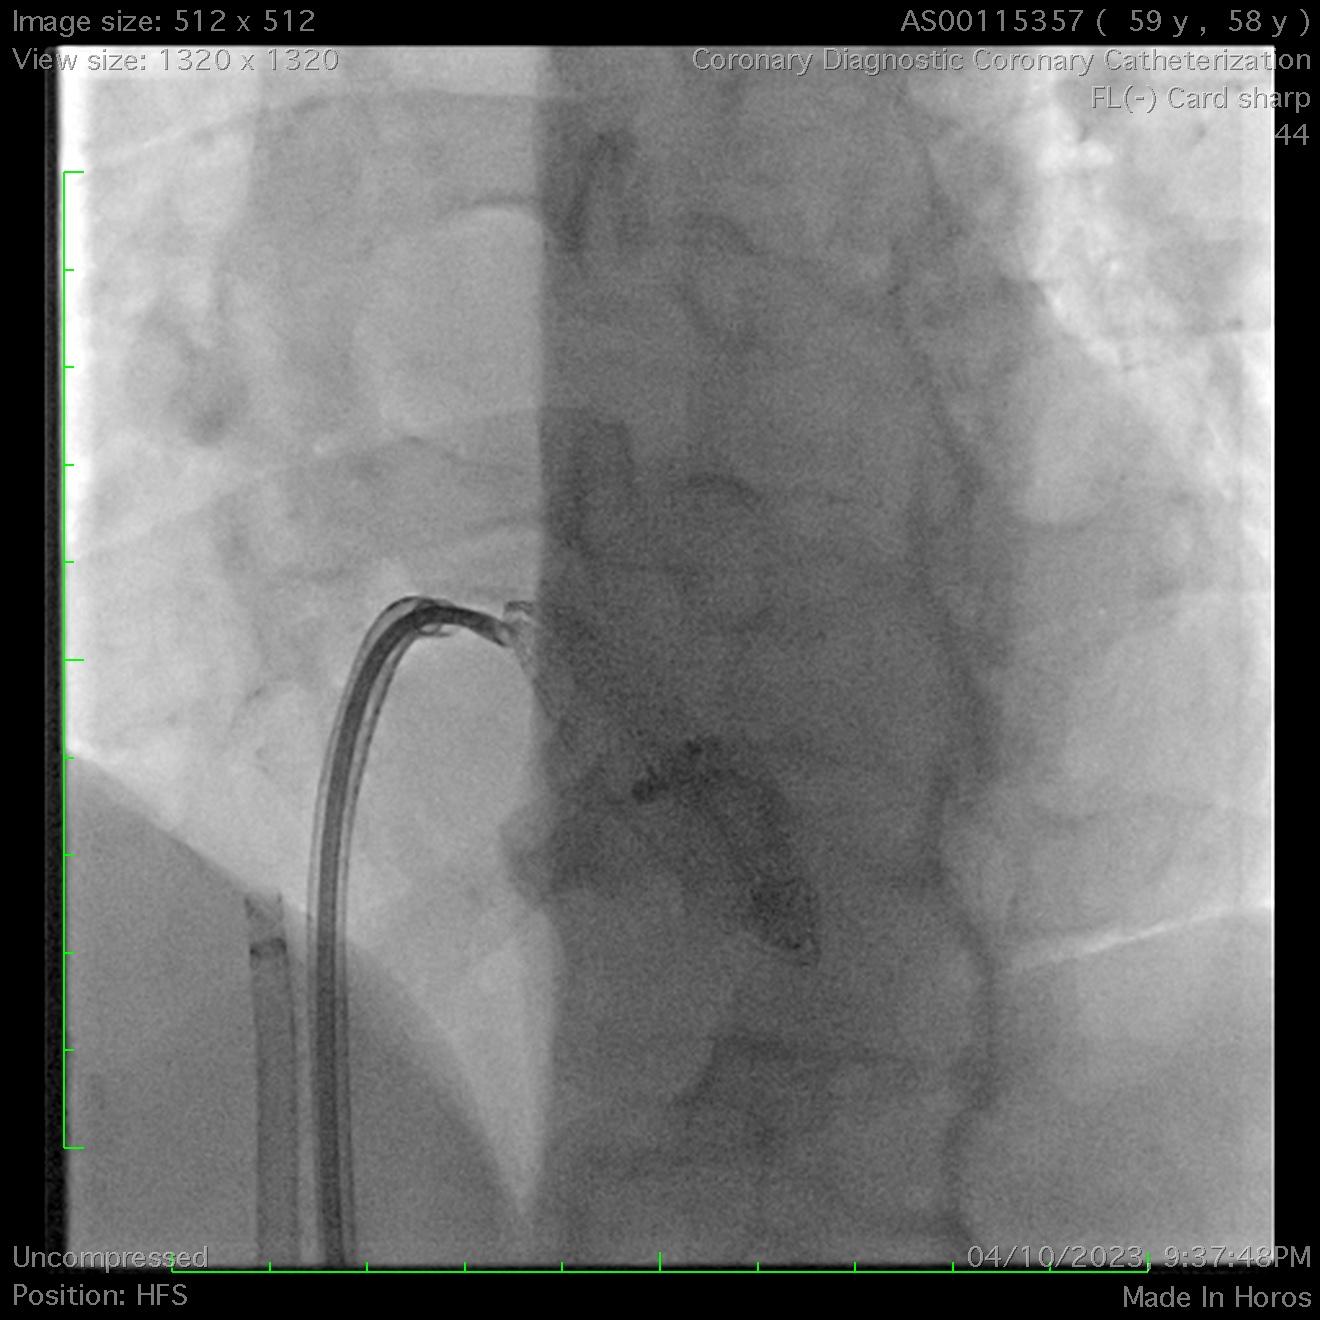

Ultimately, a biopsy forceps was used to grasp the atrial disc and pull it into the inferior vena cava. This stabilized the occluder, enabling successful snaring of the left atrial disc’s hub into the left femoral sheath. Subsequently, a second snare was deployed from the right femoral sheath to capture the right atrial disc’s hub, allowing its sheathing & subsequent removal.

A 42mm occluder was subsequently re-implanted using a balloon-assisted technique. Due to the prolonged procedure, the patient developed hemorrhagic pericarditis on the second postoperative day and required temporary pericardial drainage. The patient was discharged home three days post-procedure. Serial TTE performed on days 1, 1 month, and 6 months confirmed the occluder's in-situ position and the absence of peri-device leaks.